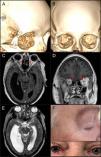

Immunoglobulin G4-related disease (IgG4-RD) is characterized by a systemic fibroinflammatory infiltrate that often involves the orbit in addition to other tissues. Thus it has to be considered in the differential diagnosis of orbital tumors. We report the clinical case of a 64-year-old woman who presented with right mydriasis, progressive proptosis and paralysis of the third cranial nerve of 1 year of evolution. Cranial MRI identified an intraconal lesion of the right orbit, located between the external and inferior rectus muscles and the optic nerve, and she was scheduled for surgery by transcranial approach with lateral micro-orbitomy. A satisfactory macroscopic excision was achieved with no remarkable complications and a definitive deferred histological result of pseudotumor by IgG4-RD. Follow-up for 24 months showed no tumor recurrence, and the patient clinically improved from ophthalmoplejia. This case highlights the efficacy of lateral orbitotomy in the etiologic diagnosis and successful therapeutic outcome of complex orbital lesions associated with IgG4-RD pseudotumor.